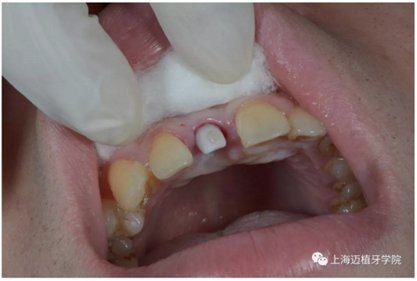

戴牙前口內(nèi)照片:

去除愈合基臺(tái):

口內(nèi)個(gè)性化基臺(tái):